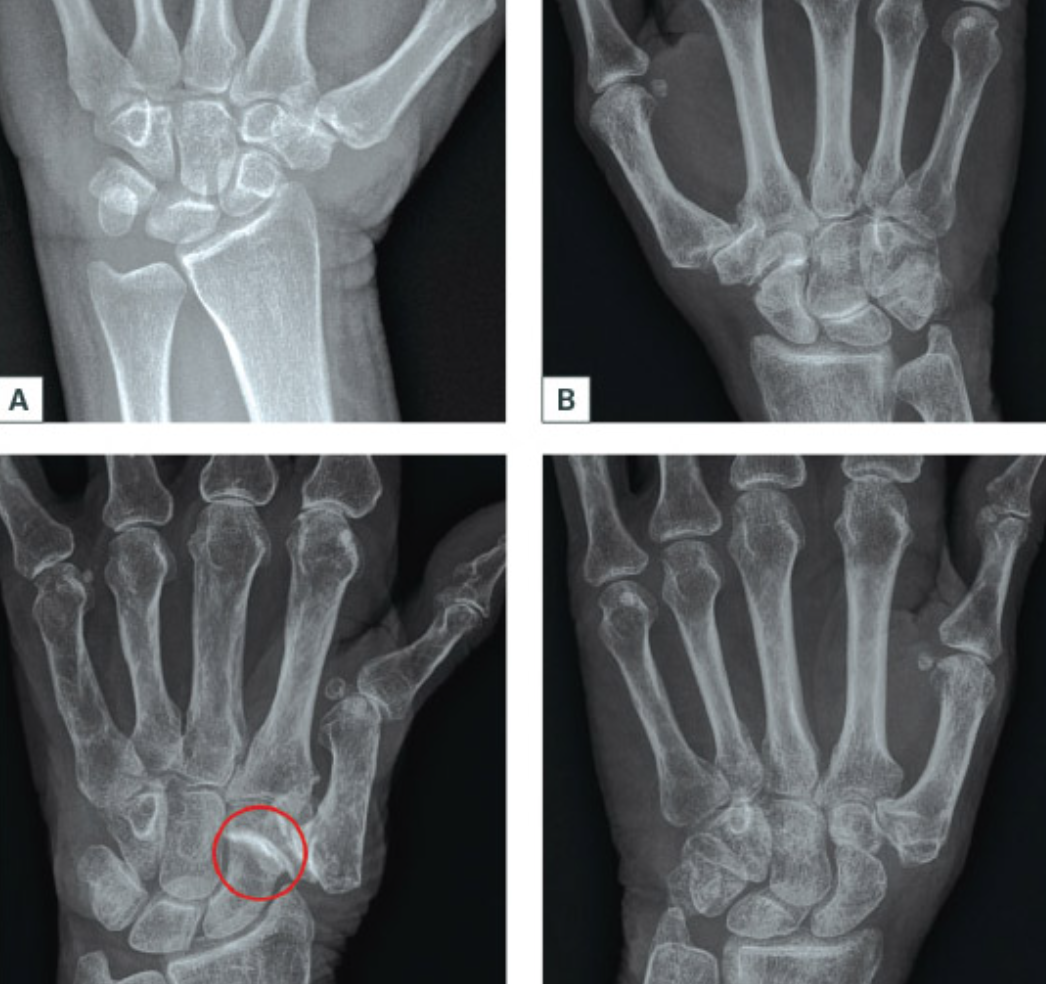

Describe the pathology here…

Right distal undisplaced Scaphoid Fracture

How to you manage a scaphoid fracture initially?

Immobilisation in a thumb spica cast

(or Immobilisation of the fracture in a below elbow / short arm / scaphoid cast)